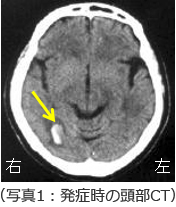

患者さんは、52歳の男性でした。右側の耳の上あたりで心臓の鼓動に一致するような「ズン・ズン・ズン」という耳鳴りを一日中感じていた。それ以外に症状はないために放置していたようです。ある日突然右側の強い頭痛があり、普段は正常な血圧が170/80mmHgと高いために受診となりました。その際の頭部CT(写真1)が右側の写真です。黄色の矢印に示す部分に脳出血をおこしています。通常の脳出血は高血圧性脳出血といって高血圧によって血管が傷むことによっておこる脳出血です。この患者さんはもともと高血圧もありませんし、通常の脳出血ではおこらないような場所に出血をおこしていましたので、違う原因が考えられました。